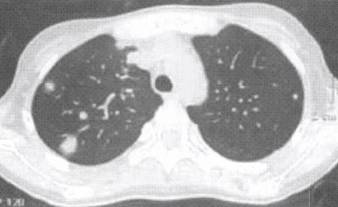

CT晕征是CT图像上肺内实性肿块灶或结节影中心密度稍高,边缘密度稍低,病灶四 周被一圈淡薄的云雾样“磨玻璃”样阴影环绕,其厚度不一,范围狭窄,呈晕圈样改变。见 图2至图4。 医学百科网 | YxBaike.Com